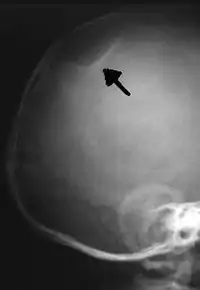

The material factual allegations of the amended complaint are as follows. Plaintiff was born on May 14, 1970. On repeated occasions during the first year of her life she was severely beaten by her mother and the latter's common law husband, one Reyes. On April 26, 1971, when the plaintiff was eleven months old, her mother took her to the San Jose Hospital for examination, diagnosis, and treatment. The attending physician was defendant Dr. Flood, acting on his own behalf and as agent of the defendant San Jose Hospital. At the time, the plaintiff was suffering from a comminuted spiral fracture of the right tibia and fibula, which gave the appearance of having been caused by a twisting force. Plaintiff's mother had no explanation for this injury. Plaintiff had bruises over her entire body. In addition, she had a non-depressed linear skull fracture which was then in the process of healing. Plaintiff demonstrated fear and apprehension when approached. Inasmuch as all plaintiff's injuries gave the appearance of having been intentionally inflicted by other persons, she exhibited the medical condition known as the battered child syndrome.

It is alleged that proper diagnosis of plaintiff's condition would have included taking X-rays of her entire skeletal structure, and that such procedure would have revealed the fracture of her skull. Defendants negligently failed to take such X-rays, and thereby negligently failed to diagnose her true condition. It is further alleged that proper medical treatment of plaintiff's battered child syndrome would have included reporting her injuries to local law enforcement authorities or juvenile probation department. Such a report would have resulted in an investigation by the concerned agencies, followed by a placement of plaintiff in protective custody until her safety was assured. Defendants negligently failed to make such report.